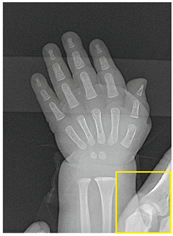

Table 2, Table 3, Table 4 and Table 5 present the results obtained through the multi-objective optimization image enhancement approach. Specifically, Table 2 and Table 3 show the results for natural images, while Table 4 and Table 5 display medical images. The tables are organized as follows: the first and second columns list the image names and their corresponding original, unenhanced versions. The third to fifth columns showcase the selected points from the Pareto front, representing the maximum contrast, knee point, and maximum detail, in that order. The final column illustrates the obtained Pareto front through the optimization process, with red, green, and orange points indicating the images that achieved maximum contrast, knee point, and maximum detail, respectively.

Table 4.

Medical image results—1.

For medical images, there are instances where differences are more perceptible. For example, in the Medical3 image, the maximum contrast solution makes it difficult to visualize the internal details of the basophil (a white blood cell highlighted in the box), which could result in a less accurate interpretation. In contrast, the knee and maximum detail solutions provide a clearer view of the interior of the white blood cell. Similarly, in the Medical5 image, the maximum contrast solution highlights the hand and arm bone structures. However, the maximum detail image offers a more precise view of the internal structures within the bones (see the highlighted region), which is crucial for a more detailed evaluation. Another notable example is the Medical8 image, where the maximum detail solution offers a more detailed view of the internal structure of the eosinophil (another type of white blood cell). However, the maximum contrast image improves the visibility of red blood cells. As shown in the yellow box, this solution reveals a red blood cell that is nearly imperceptible in the other solutions. An interesting case is the Medical6 image, where only a few non-dominated solutions are present on the Pareto front. Despite the similarities among the preferred solutions, the nodules are much more perceptible in the enhanced images than in the original image, as observed in the highlighted region.